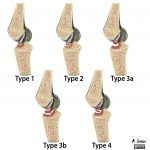

Chấn thương khớp gối là một trong những thương tích hay gặp nhất trong thể thao, lao động và sinh hoạt. Nếu không được chẩn đoán, xử trí đúng đắn, kịp thời, chấn thương gối dễ để lại những hệ quả phiền toái cho người bệnh, ảnh hưởng đến chức năng vận động của khớp. Khớp gối là một khớp bản lề, lớn nhất cơ thể, nằm ngay dưới da, bao gồm đầu dưới xương đùi, đầu trên xương chầy và xương bánh chè…